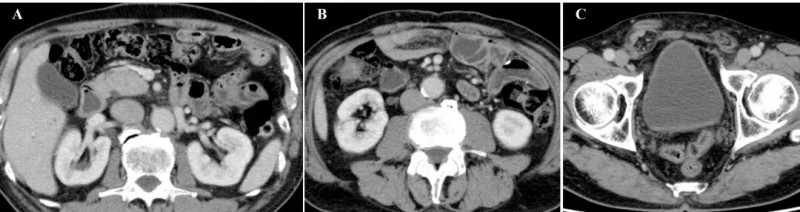

而在完成第6次治疗后,患者症状大幅改善。最终在第8次治疗后1个月,恶性腹水完全消失,腹胀、腿部水肿消退,食欲恢复,原发病灶与转移性淋巴结持续缩小,腹膜播散的影像学特征已不明显——腹腔内脂肪性粘稠组织大网膜消失(详见下图A),腹水消退(详见下图B),仅右侧腹股沟疝因之前大量腹水导致的腹压仍持续存在(详见下图C)。

▲图源“Cureus”,版权归原作者所有,如无意中侵犯了知识产权,请联系我们删除